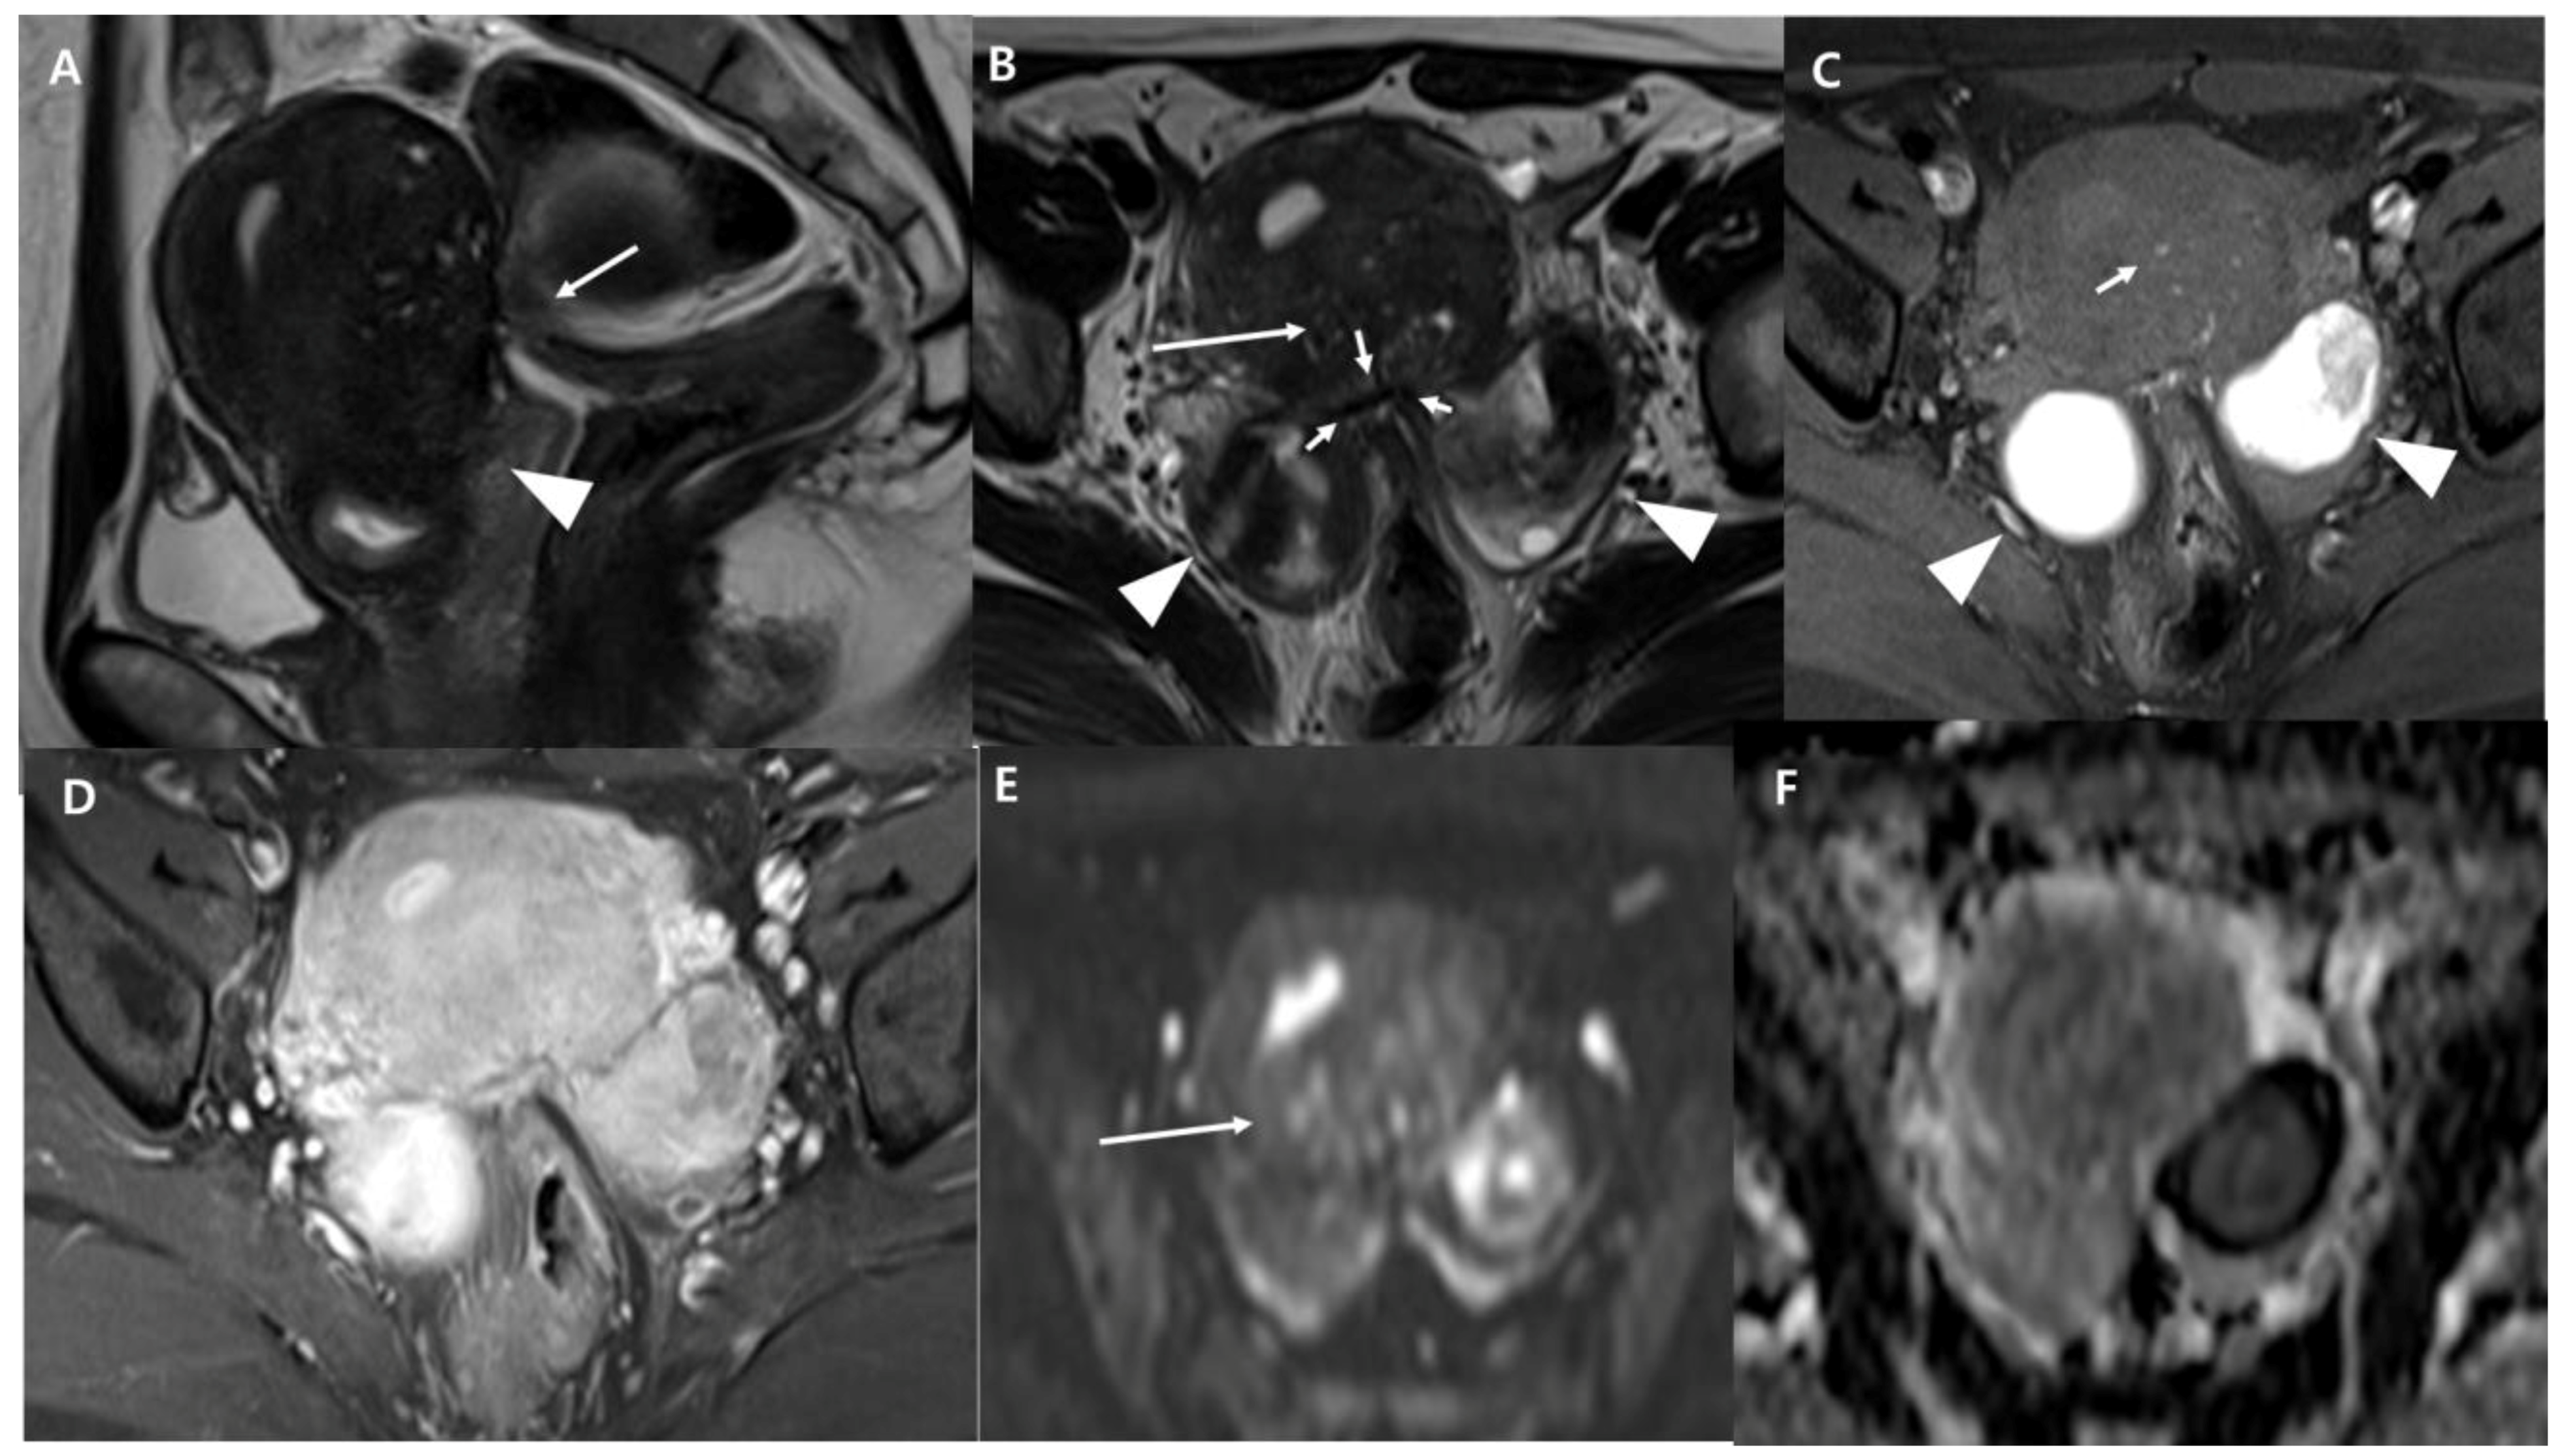

2.2. MRI Examination and Image Analysis